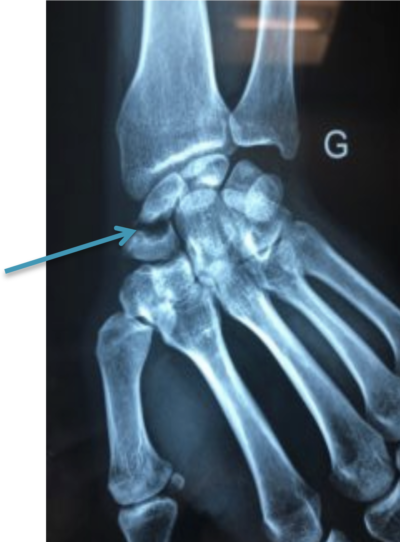

Fracture du scaphoïde

Le scaphoïde est un des osselets du poignet (carpe). Le scaphoïde s’articule avec le radius. Il se trouve entre la base du pouce et le poignet.La fracture du scaphoïde est la plus fréquente des fractures des os du carpe. Elle survient lors d’une chute sur la main en extension de poignet.

Fracture deu scaphoïde

Elle passe fréquemment pour une entorse de poignet, et son diagnostic est parfois méconnu lors d’un premier examen par un médecin ou posé tardivement. Le diagnostic pourra être fortuit lors de la réalisation d’une radiographie suite à un autre traumatisme ou lors de la persistance de douleurs plusieurs mois ou années après un traumatisme.

Il faut réaliser une radiographie du poignet. En cas de doute, on peut réaliser un scanner qui permettra d’affirmer ou d’exclure le diagnostic de fracture du scaphoïde.